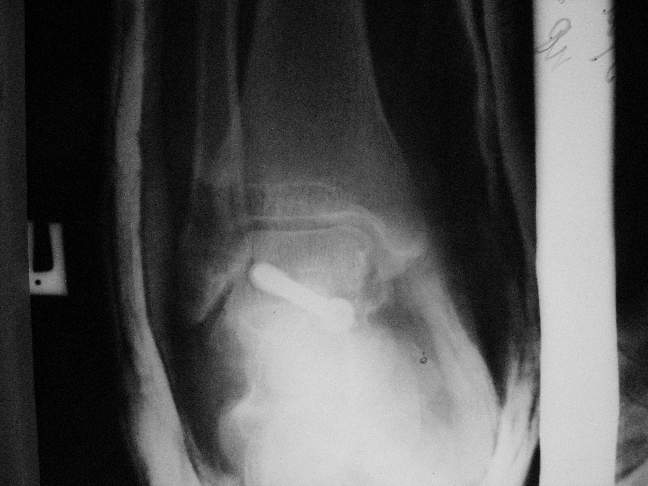

Здесь на фото примеры:

Переломовывих тарана с повреждением медиальной стороны. Через 4 часа после

поступления проведена репозиция и фиксация тарана после

Irrigation&Debridment. Частичное несращение медиальной лодыжки не беспокоит,

вернулся к активному образу жизни. Полная нагрузка разрешена через 11

недель. Финальные снимки через 11 месяцев.